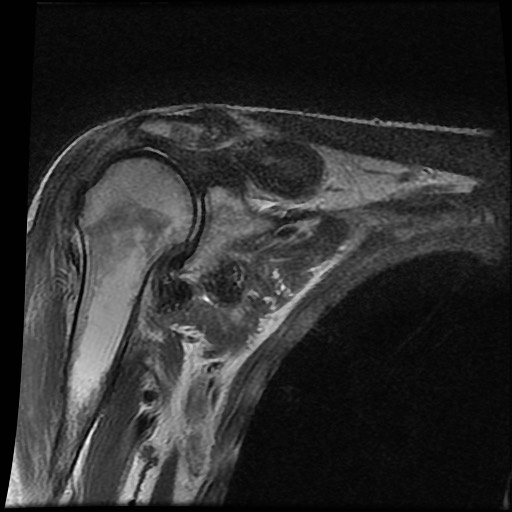

Tiếp tục xem hình ảnh MRI của bệnh nhân này.

Hình ảnh MRI:

Tràn dịch lan tỏa tất cả các khớp cổ tay.

Phù tủy xương lan tỏa tất cả các xương cổ tay.

Bào mòn xương, ví dụ tại xương thuyền, xương đầu và xương móc.

Phá hủy khe khớp và sụn khớp, rõ nhất tại khớp STT và CMC4/5.